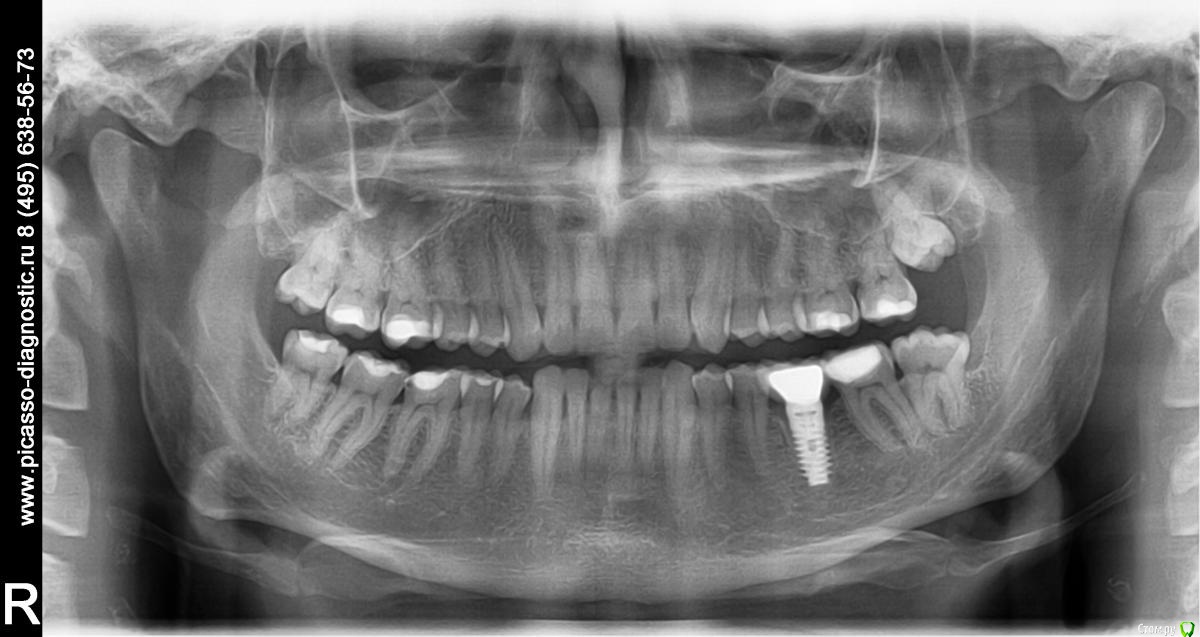

VladV Опубликовано 19 апреля, 2015 Поделиться Опубликовано 19 апреля, 2015 Помогите, пожалуйста, советом. Заранее извиняюсь за простыню. Около полутора месяцев назад пропустил два удара в голову. Один пришелся в верхнюю челюсть, другой в районе правой брови. Была сильно разбита верхняя губа, которая слиплась и срослась сама (не зашивали). Зубы, вроде бы, не беспокоили. Проверял холодом - реакция есть. Явных болевых ощущений не было, но как-то стал чувствовать верхнюю единицу (11), иногда совсем чуть-чуть зуб поднывал и было ощущение, что совсем немного сдвинулся назад, внутрь рта (возможно, всегда таким был, не обращал внимания). При смыкании зубов поверхностью верхнего к поверхности нижнего, а не нижний за верхний, явной боли не было, но я старался не смыкать лишний раз и не кусать этими зубами. Губа зажила где-то через две недели, только внутри уплотнение небольшое осталось. Не знаю, важно ли, но примерно после заживления губы то ли словил вирус, то ли есть связь с зубами, но начался сильный насморк, который длился недели две и вторая неделя была с густыми зелеными (простите за подробности) выделениями и даже иногда кровь шла из носа от попыток их вымыть и высморкать.Спустя месяц, когда насморк прошел, решил сходить к стоматологу в частную клинику и проверить зубы на всякий случай, т.к. непонятные ощущения в 11 зубе остались. Простучали зубы 22-21-11-12. У всех зубов чувствительность одинаковая, у 11 чуть сильнее. Сделали несколько прицельных снимков. Врач ничего криминального с корнями не обнаружил. Посоветовали сделать чистку зубов ультразвуком и AirFlow, т.к. был сильный налет и отложение камня.Через пару дней сделал чистку. Полтора часа чистили все зубы, так как около 5 лет до этого не чистил. Врач долго не мог понять, что за смолянистый темный налет был на зубах (не курю и кофем не злоупотребляю), в итоге выяснили, что из-за постоянного полоскания ротовыми ополаскивателями, содержащими хлор. Увлекался ими последние полгода. После травмы зуба казалось, что после ополаскивания зубу легче становилось и его долго ничего не беспокоило. Во время осмотра между верхними единицами обнаружился легкий кариес. Врач сказал, что на корни и мои ощущения 11 зуба он никак влиять не может. После чистки местами были травмированы десны, местами маленькие гематомы были, некоторые зубы стали особенно чувствительно переносить холодное и горячее. Но то ли так совпало, то ли из-за чистки, 11 зуб стал чаще поднывать, причем, непонятные ощущения переместились ближе к пространству между 11 и 12 зубом, и на 12 зуб вроде бы тоже стали распространяться. Сложно описать, но такое ощущение, что чувствительность куда-то ближе к носу ушла, иногда как будто напряжение какое-то между зубами возникало, будто еда застряла. Стал непроизвольно тсыкать - прислонять язык к щели 11-12, 11-21, 12-13 и втягивать резко воздух, так легче что ли становилось или из-за ощущений от увеличенных просветов между зубами. Потом то ли из-за того, что не пользуюсь передними зубами, то ли из-за чего-то другого, но появилось ощущение, что изменился прикус. Нижние единицы стали как-то ощутимее упираться в верхние единицы, будто в другом месте из-за якобы ушедшей чуть-чуть вперед нижней челюсти. Иногда верхние единицы становились как чужие, снижалась чувствительность что ли. Иногда кажется соленоватый привкус у десны между 11 и 12 зубами, хотя крови и каких-либо выделений в слюне нет. В какие-то дни эти ощущения уходили, в какие-то возвращались. Заметил, что у 11 зуба есть небольшая подвижность, определил прислоняя палец к щели 11-12 и сжимая/расслабляя челюсти. Понаблюдав неделю пошел уже в другую частную клинику. Там опять сделали снимки (прилагаю к сообщению), опять ничего криминального не обнаружили. Кариес легкий между 11 и 21 видят, рекомендуют убрать и отреставрировать зубы, но не видят связи с моими ощущениями. Сказали, наблюдать дальше за зубом, сделать контрольные снимки месяца через три и не заморачиваться. Легко им говорить, у меня уже паранойя развиваться начала. Каждое утро просыпаюсь и сразу прислушиваюсь к ощущениям, потом весь день то отвлекаешься, то опять вспоминаешь и тсыкаешь. Все еще осложняется тем, что в двадцатых числах я почти на 20 дней улетаю в Египет, где если и случится чего, то вряд ли смогут квалифицированно помочь с зубами.В итоге решил поискать информацию в Интернете и наткнулся на этот форум. Начитался ужасов всяких и еще больше теперь боюсь уезжать. Правда, непонятные ощущения после этого стали реже возвращаться, уже пару дней, испугались, наверно. Записался на панорамный снимок, который и прикладываю. Прошу специалистов высказать свое мнение. Действительно ли забить и жить с этими непонятными ощущениями или дальше копать. Какие препараты лучше взять на случай, если что-то пойдет не так в поездке? Заранее спасибо за рекомендации и еще раз простите за простыню. Ссылка на комментарий